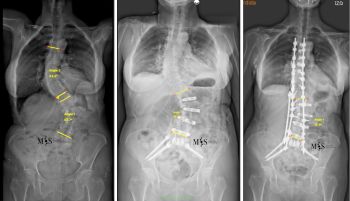

El equipo quirúrgico del Centro Médico Teknon, liderado por el Dr. Christian Morgenstern, director del Morgenstern Institute of Spine en Centro Médico Teknon, ha intervenido con éxito a una paciente de 80 años afectada por una escoliosis degenerativa dorsolumbar severa. El caso, que presentaba una curvatura de 57º en la zona lumbar y 42º en la dorsal, ha sido resuelto mediante la técnica ACR (corrección de columna anterior) en dos tiempos.

La intervención se dividió en dos tiempos quirúrgicos para maximizar la seguridad. En una primera fase, se realizaron abordajes mínimamente invasivos por vía anterior y lateral para rectificar parcialmente la columna, por lo que se logró reducir la curva lumbar de 56º a 39º de forma inmediata. Esta corrección previa permitió que la segunda fase, realizada por vía posterior, fuera mucho menos agresiva y pudiera ejecutarse de forma percutánea.

Para garantizar la seguridad en una anatomía tan compleja, donde las vértebras presentaban rotaciones tridimensionales y pedículos muy finos, se usó tecnología de neuronavegación y TAC intraoperatorio (O-Arm). Estas herramientas permiten una colocación milimétrica de los implantes y minimizan el riesgo de lesiones nerviosas o vasculares. En casos como este, este tipo de tecnologías juegan un papel clave. Según apunta el Dr. Morgenstern "en las rotoescoliosis complejas como esta la anatomía puede ser muy variable y compleja, puesto que las vértebras están muy rotadas en un espacio tridimensional. Además, los pedículos pueden ser displásicos, muy finos o muy frágiles. La neuronavegación con el TAC intraoperatorio permite una colocación mucho más segura de los tornillos transpediculares en anatomías tan complejas al ofrecer imágenes en las 3 dimensiones anatómicas".